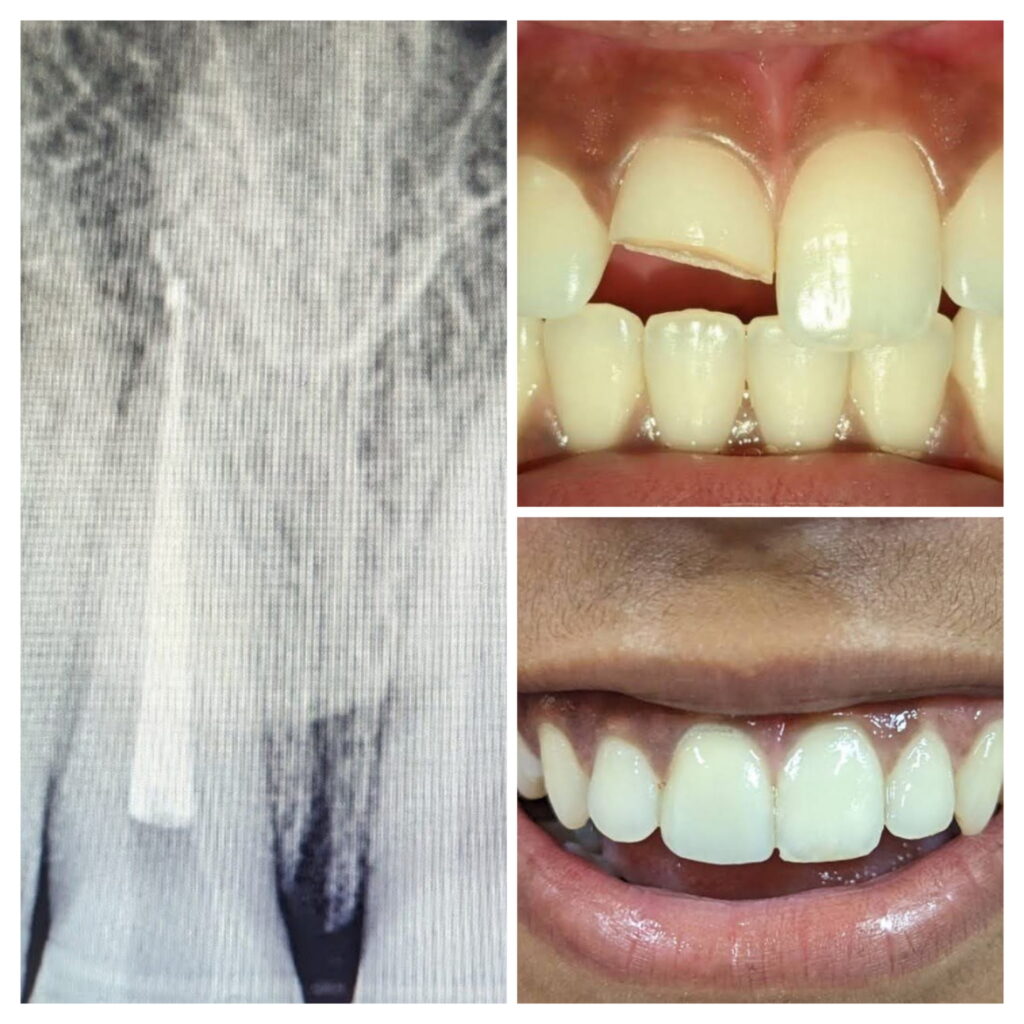

He has developed particular expertise in managing complex endodontic cases, including retreatments and the correction of iatrogenic errors and procedural mishaps. His clinical proficiency extends to the restoration of severely compromised teeth, ensuring both functional and aesthetic rehabilitation. Dr. Shankar is a firm advocate of advanced dental protocols, routinely incorporating rubber dam isolation and magnification techniques to enhance treatment accuracy, patient safety, and long-term outcomes.

- Endodontic retreatment

- Management of iatrogenic errors / mishaps

- Restoration of badly broken down teeth

- Magnification-assisted endodontics

Root canal Treatment Using Microscope And latest instruments

Composite Restoration

Post and Core And Smile Designing